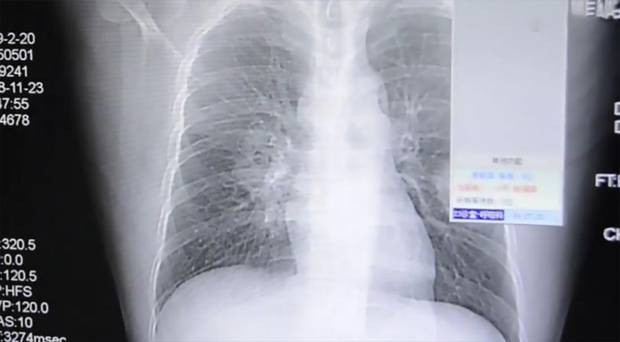

Fujian Eyaletinde yaşayan , 37 yaşındaki hasta, göğüs ağrıları ve öksürükşikayeti ile hastaneye yatırıldı. Doktorlar ayakta olan bir cins mantarın ciğerde yaşadığını fak edince şok oldular.

Çekilen röntgen görüntülerinde de açıkça görülen mantarın nedeni zayıf bağışıklık sistemi ve sürekli koklanan kirli çoraplar olarak gösterildi.